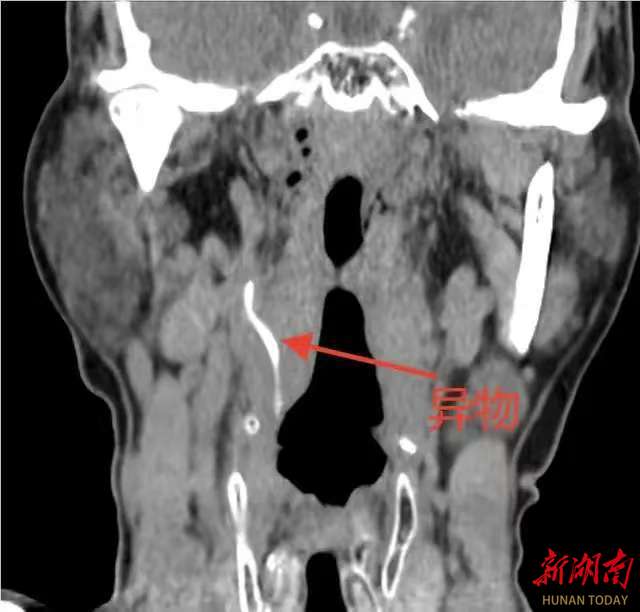

科主任陈志军接诊患者后,结合喉镜情况及详细询问病史,判断该异物可能已深入颈内间隙,经颈部CT三维重建检查,提示咽侧壁异物已穿破黏膜层,深入颈部间隙,且异物尖端距离右侧颈动脉分支仅毫厘之遥。颈动脉是大脑供血的主要通道,一旦被异物刺破或继发感染侵蚀血管,极易引发致命性大出血或脑卒中,手术风险极高。影像警示:异物如同一枚“定时炸弹”,静静地潜伏在颈动脉分支旁,每一次吞咽、颈部活动都可能带来不可预料的危险。面对如此棘手的情况,陈志军科主任迅速启动应急预案,组织血管外科、麻醉科进行多学科会诊。发现风险,经分析,异物位置较深,周围重要血管、神经密布,传统颈外径路手术创伤大、易损伤血管,且可能因术中移位导致二次伤害。

当时,医院利用长柄精细器械,巧妙避开血管搏动区域,以毫米级精度缓缓牵拉,最终将一枚长约4cm的弧形鱼骨完整取出。术中,即刻检查术野无明显活动性出血,颈动脉搏动良好,术后复查CT确认异物无残留,邻近血管毫发无伤。出院当天,受到来自患者及家属的点赞。